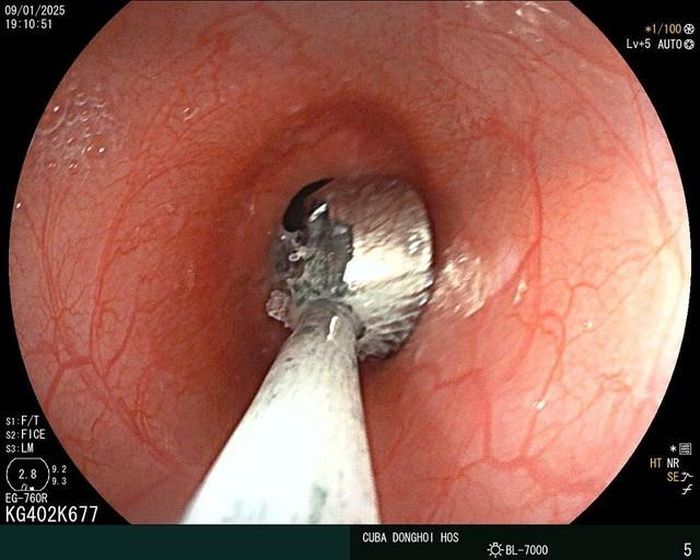

Vào lúc 19h cùng ngày, bằng phương pháp nội soi gây mê đường tiêu hóa, các bác sĩ khoa Thăm dò chức năng - Nội soi Bệnh viện Hữu nghị Việt Nam - Cu Ba Đồng Hới đã tiến hành nội soi thuận lợi và lấy ra được dị vật đang nằm tại phình vị dạ dày người bệnh. Dị vật được xác định là loại pin hình tròn có đường kính 0,6cm đang có dấu hiệu bị ăn mòn.

Dị vật nằm trong đường tiêu hóa của bé gái 19 tháng tuổi.